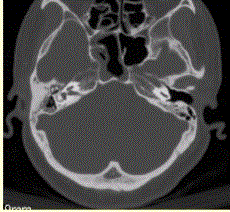

问题 患者男,20岁,外伤后右耳听力下降伴面瘫7d。临床检查,右耳传导性耳聋,发现脑脊液耳瘘。CT表现如下图。 颞骨HRCT的主要技术参数不包括

选项 A.薄层扫描(1~2mm) B.重建矩阵不低于512×512 C.骨重建算法 D.小扫描野或靶扫描 E.高mA扫描

答案 E